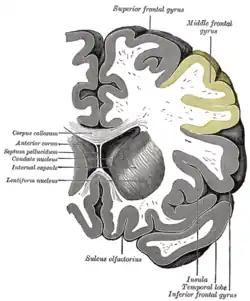

Coronal section through anterior cornua of lateral ventricles. | |

| Part of | Frontal lobe |

| Artery | Middle cerebral |